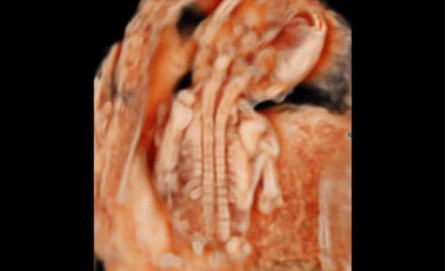

3D/4D成像方面,Hera i 10通過結(jié)合先進(jìn)的圖像渲染技術(shù),著重加強(qiáng)了邊緣和小結(jié)構(gòu)的可視化能力。